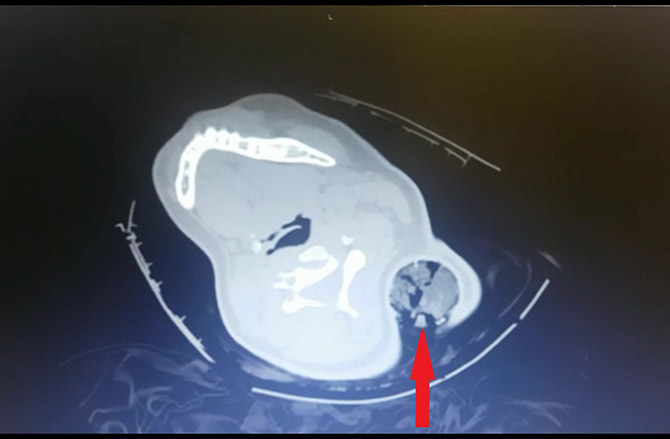

31 Temmuz 2019 da başka bir aracın sıkıştırması sonucu kaza geçiren aracın yolcu koltuğunda oturan 19 yaşındaki B.Ö.’nün boynuna saplanan 30 santimetrelik tahta kazık sol koltuk altından çıktı. Tahta kazığı ameliyatla çıkaran KSÜ Tıp Fakültesi Ortopedi ve Travmatoloji Anabilim Dalı Öğretim Üyesi Dr. Bülent Güneri, genç kızın sadece bir kaburgasının kırıldığını, sinir ve damarlarının zarar görmediğini belirterek, "Tıp literatüründe bu şekilde boyundan girip koltuk altından çıkan bir cisim yok" dedi.

Kazada ağır yaralanan genç kız, vücuduna saplanan tahta kazık ile KSÜ Tıp’a götürüldü. Hastaneye bilinci açık olarak gelen B.Ö.’ye acilde yapılan ilk değerlendirmenin ardından acil hekimlerince Ortopedi ve Travmatoloji Anabilim Dalı Öğretim Üyesi Dr. Bülent Güneri’ye haber verdi. Hastanın yanına gelen Güneri, çekilen tomografi görüntülerini inceledikten sonra genç kızı ameliyata aldı. Yaklaşık yarım saat süren ameliyatla tahta kazık çıkarılırken, kazığın sinir ve damarlara zarar vermemesi nedeniyle mucize eseri hayatta kalan genç kız olayı bir kaburga kırığı ile atlattı. B.Ö. hastanede gördüğü bir haftalık tedavi sonrası sağlığına kavuşarak taburcu edildi.

Bu tür vakalarda genellikle sinir ve damar yaralanmalarının olduğunu ancak bu olayda sinir ve damar yaralanmasının olmayışının çok ilginç olduğunu ifade eden Güneri, “Hastayı acil ameliyata aldık. Ameliyat esnasında Göğüs Cerrahisi hocamız Dr. Öğretim Üyesi Ahmet Acıpayam ve Kalp ve Damar Cerrahisi hocamız Doç. Dr. Mehmet Acıpayam hazır bulundular herhangi bir komplikasyona yönelik olarak. Ameliyathanede yaptığımız değerlendirmeden sonra anestezi altında yaklaşık 30 santimetrelik tahta bir kazık çıkardık hastadan. Kazık, hastanın saçlarını dolayarak boynundan girip sol kol altından çıkmıştı. Ve böyle kirli bir yaralanma, ev dışında, sokakta olan bir yaralanma enfeksiyon açısından oldukça risklidir. Ama ameliyat esnasında yaptığımız girişimler ve titizlikle uyguladığımız antibiyotik tedavisi sayesinde hastamızda bir enfeksiyon meydana gelmedi” diye konuştu.

Olayın çok ilginç olması nedeniyle daha önce bu ve buna benzer bir vakanın olup olmadığını araştırdığını belirten Dr. Bülent Güneri, şöyle devam etti: “Tıp literatüründe benzer yaralanmalar var, metal ve tahta cisim saplanmaları görülüyor. Ancak bu şekilde boyundan girip koltuk altından çıkan bir cisim yaptığım taramalarda tespit etmedim. Ancak literatürde bildirilen vakalarda çok ciddi sinir yaralanmaları ya da omuriliğe saplanıp da enfeksiyona yol açan bu nedenle tedavi görmek zorunda olan hastalar mevcut. Bizim hastamızda herhangi sinir veya damarsal yapıya denk gelmedi ancak bir kaburga kırığına yol açtı ve içeride bol miktarda hastanın saç bulunduğu için bizi daha çok uğraştıran içeride bulunan saç parçalarıydı. Biz, kazığın gidiş yönü boyunca açmayıp, kazığı ters yönde çıkartıp içeriye bol miktarda steril sıvıyla yıkama uyguladık ve iyi bir antibiyotik tedavisi verdiğimizi düşünüyorum. Bu sayede de bir sorun meydana gelmedi. Hasta oldukça talihli bene, birçok kişi bunu mucize olarak değerlendirebilir. Beni ve ekibimi oldukça şaşırttı. Ve hastayı birlikte değerlendiren cerrahi branştan diğer hocalarımızı da oldukça şaşırttı. Adeta mucize gibiydi diyebilirim.”